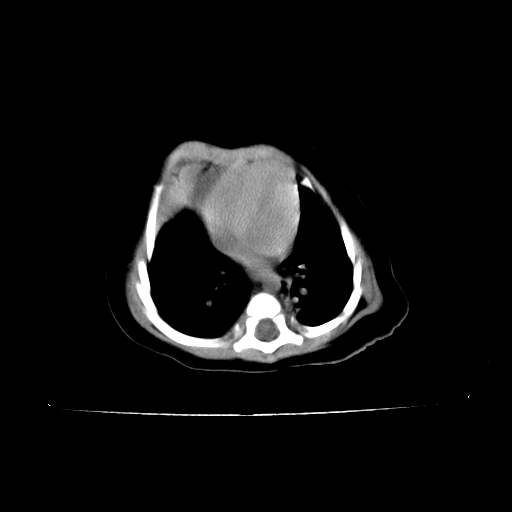

以下是引用影像之路在2009-5-8 15:46:00的发言:[br]1)胸廓畸形。2)考虑两肺感染性病变,并右肺上中叶肺不张;建议抗炎治疗后复查。3)胸腺肥大。4)前上中纵隔占位性病变待排;建议追踪复查。

以下是引用余辉在2009-5-8 8:44:00的发言:[br]鸡胸,胸腺肥大,双肺感染性病变,结合病史支原体肺炎可能性大